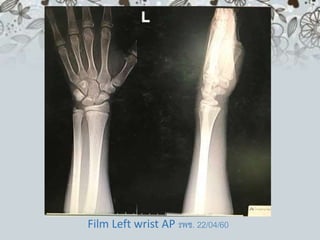

Film Left wrist AP รพช. 22/04/60

Film Left wristAP รพช. 22/04/60